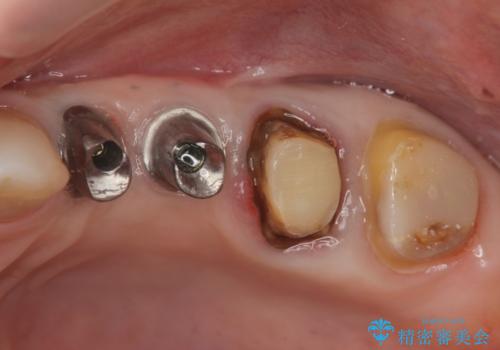

- 違和感や疼きのある左側小臼歯に加え全体的にクラウンや詰め物のやりかえを希望され来院されました。

治療後に再発した虫歯や根管再治療に加え、穴の空き症状のある上顎左側小臼歯は抜去を行いインプラントによる機能回復治療を計画します。

X線写真検査ではわからない虫歯も外してみると再発していることがあります。虫歯を丁寧に取り除き、再発を防ぐべく精密なクラウンの作製を行うことが長期的な予後につながります。